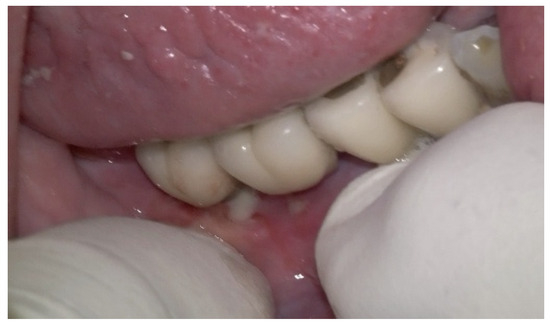

Before the surgical management following the Quadrant protocol, the fixed prosthesis was removed (Figure 20), and the region was cleaned. The surgical procedure involved a BSF, which was reflected lingually (Figure 21a,b) to facilitate access to the affected implant surfaces. With optimal access, thorough removal of granulation tissue occurred, minimizing the risk of lingual nerve damage and allowing for control of the flap.

Figure 21. (a) BSF performed; (b) BSF raised and reflected to the lingual side, exposing the implants.